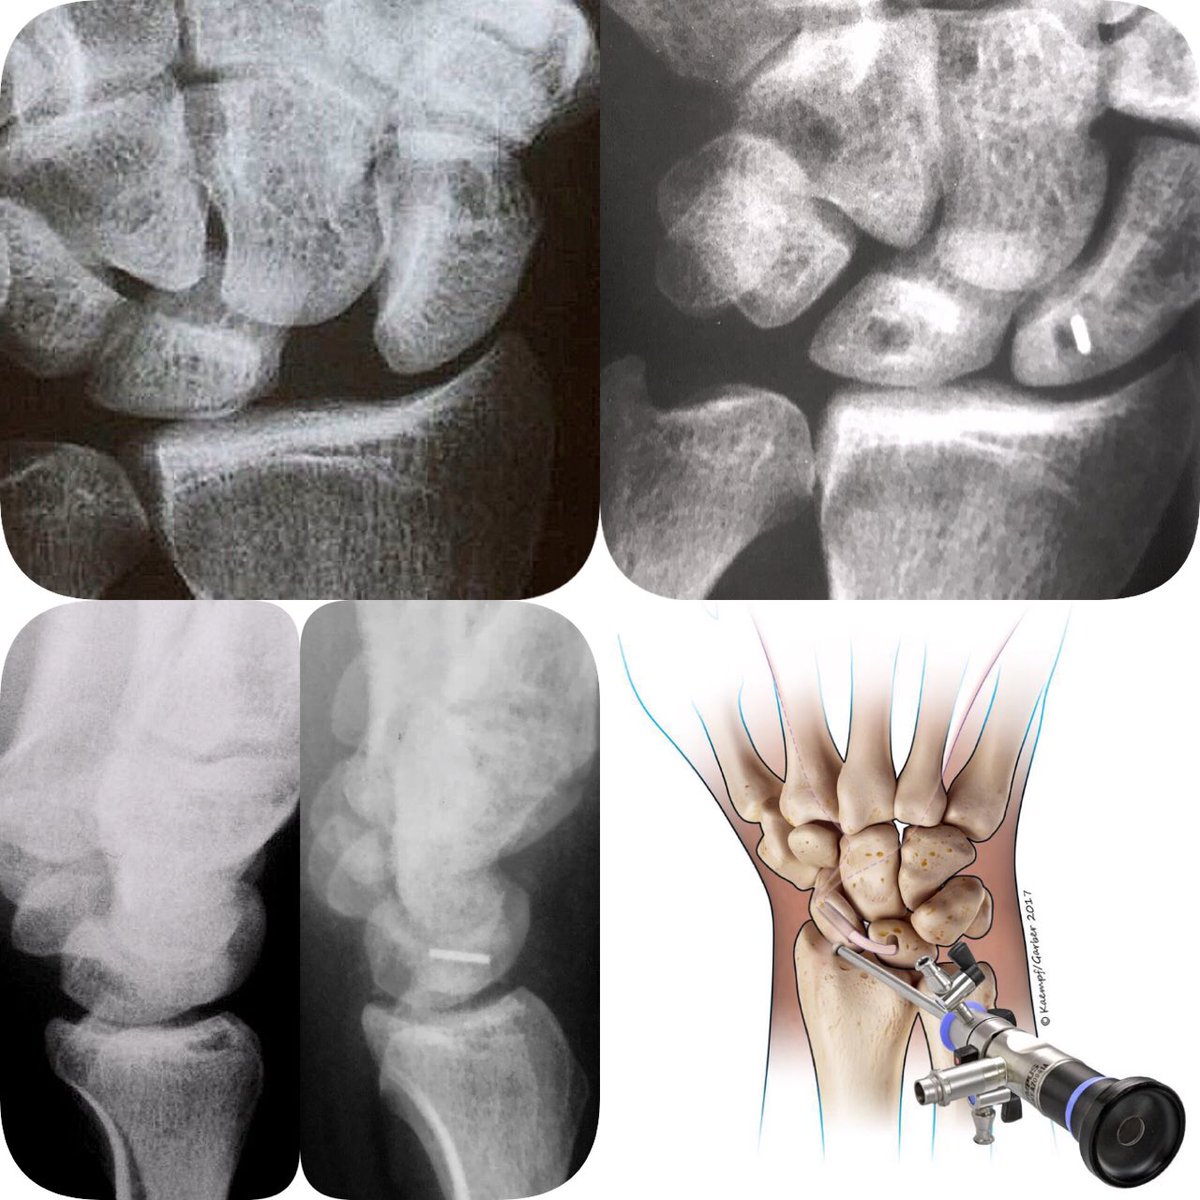

#LesãoLigamantarnoPunho Hoje em dia já se pode tratar e reconstruir as lesões crônicas do ligamento escafo-semilunar com técnica artroscópica Dr. Fernando Corella Vicente Carratalá e Marcio Aita Em caso de dor no punho, procure um #CirurgiãodeMão #HandSurgery #EWAS #SinaldeTerryThomas #DISI